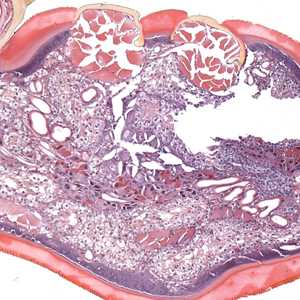

A skin biopsy specimen was collected from the clavicle region of a 45-year-old male who presented with what appeared to be a pigmented lesion. The patient resides in Kentucky and has no known international travel. The biopsy specimen was sent to Pathology for routine histologic work-up. Objects suggestive of an organism were examined on slides stained with hematoxylin-and-eosin (H&E). The attending pathologist captured images and sent them to CDC-DPDx for diagnostic assistance. Figures A-E represent five of the images received. What is your diagnosis? Based on what criteria?

Figure A